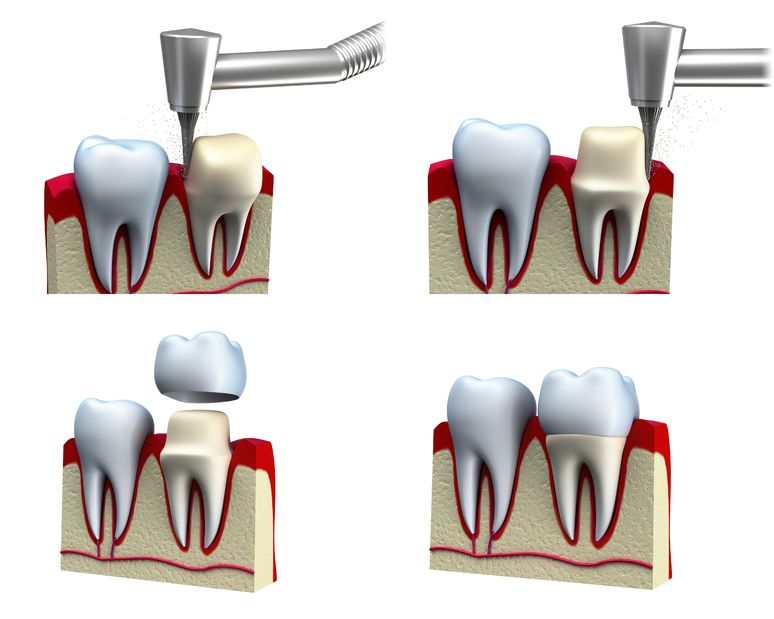

Restoring Smiles with the Benefits of Crowns & Bridges at Altamash Dental Clinic

Your healthy, confident smile is more than about looks—it influences your speech, chewing function, and entire oral health.